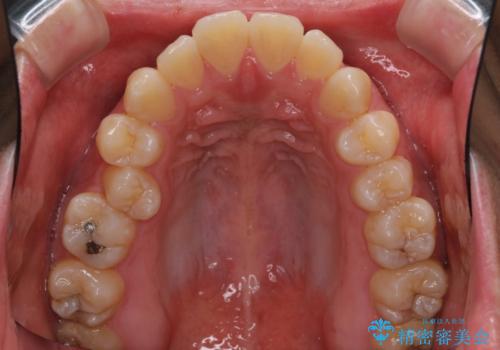

- 全体的なデコボコと、前歯の前に出ている感じを気にして来院された患者様です。

患者様と相談の上、非抜歯にてインビザラインを用いて矯正治療を行うこととし、IPR(歯と歯の間)並びに歯列全体の後方移動により口元の突出感の改善することとしました。